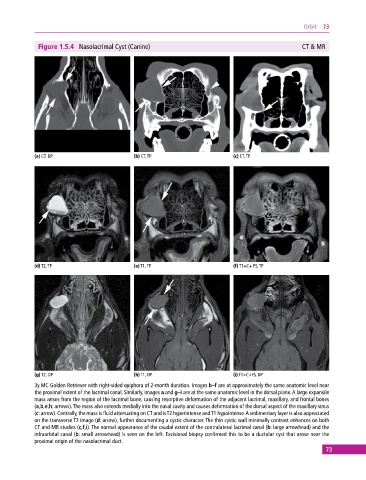

Figure 1.5.4 Nasolacrimal Cyst (Canine) CT & MR

(a) CT, DP (b) CT, TP (c) CT, TP

(d) T2, TP (e) T1, TP (f) T1+C+ FS, TP

(g) T2, DP (h) T1, DP (i) T1+C+FS, DP

3y MC Golden Retriever with right‐sided epiphora of 2‐month duration. Images b–f are at approximately the same anatomic level near

the proximal extent of the lacrimal canal. Similarly, images a and g–i are at the same anatomic level in the dorsal plane. A large expansile

mass arises from the region of the lacrimal bone, causing resorptive deformation of the adjacent lacrimal, maxillary, and frontal bones

(a,b,e,h: arrows). The mass also extends medially into the nasal cavity and causes deformation of the dorsal aspect of the maxillary sinus

(c: arrow). Centrally, the mass is fluid attenuating on CT and is T2 hyperintense and T1 hypointense. A sedimentary layer is also appreciated

on the transverse T2 image (d: arrow), further documenting a cystic character. The thin cystic wall minimally contrast enhances on both

CT and MR studies (c,f,i). The normal appearance of the caudal extent of the contralateral lacrimal canal (b: large arrowhead) and the

infraorbital canal (b: small arrowhead) is seen on the left. Excisional biopsy confirmed this to be a ductular cyst that arose near the

proximal origin of the nasolacrimal duct.